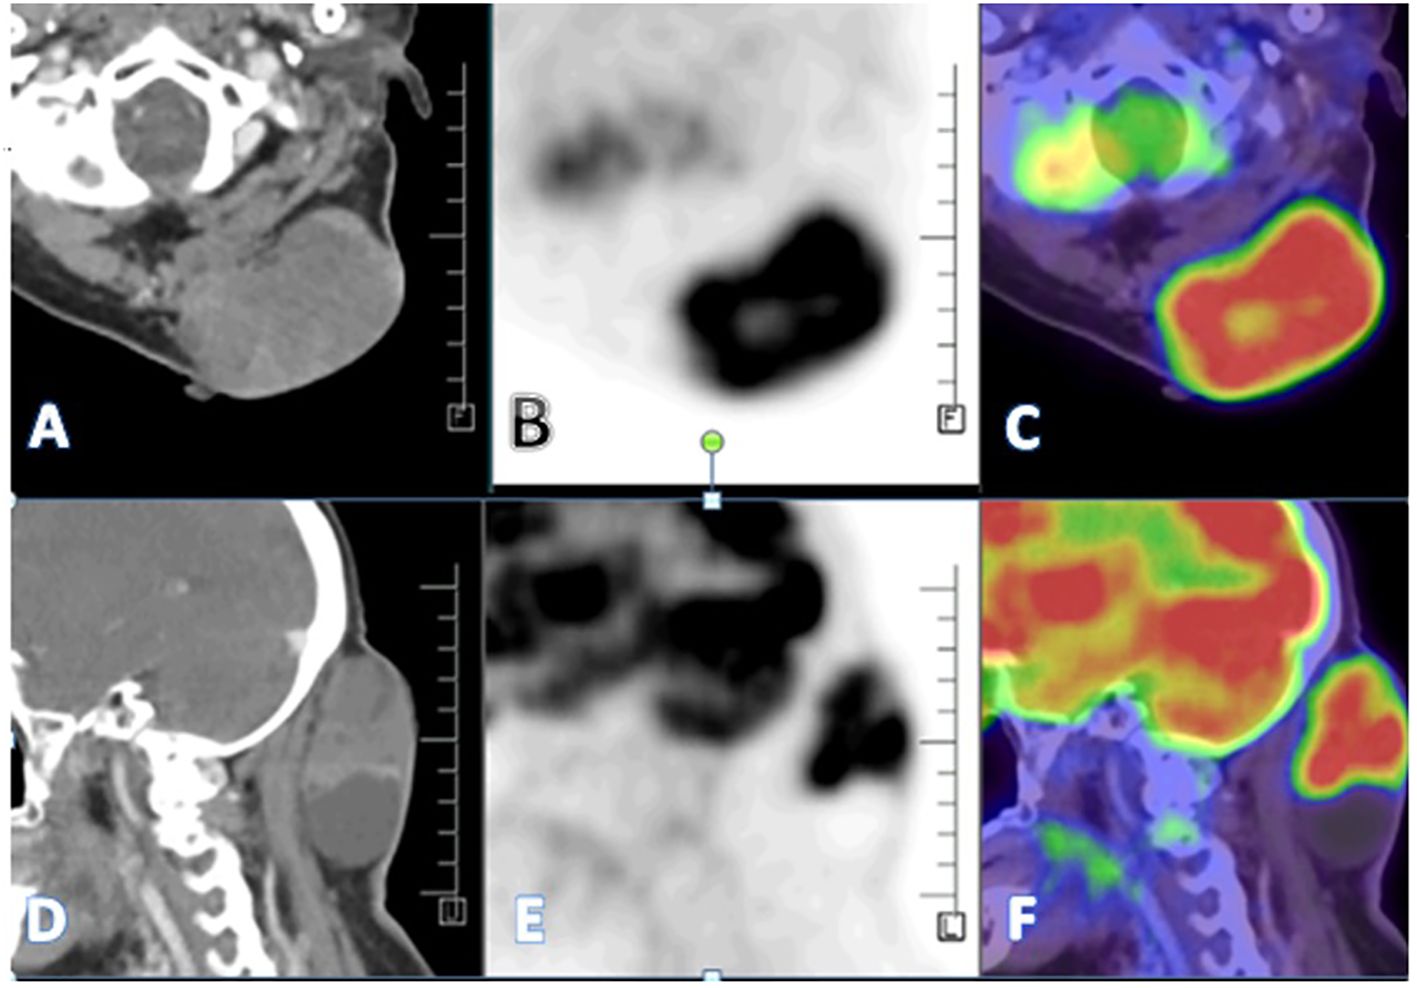

A PET CT scan showed multiple FDG-avid, malignant-looking lesions in the outer quadrant of the right breast (Figures 2A–C); right level I, II, and III axillary lymphadenopathy; and a large, malignant-looking solid cystic lesion on the left side of the nape of the neck, involving the scalp and closely abutting the underlying muscles (Figures 3A–F). With all the above data, the patient was diagnosed with a HER2-positive Invasive mammary carcinoma (mcT4bN1M0) and Malignant proliferating trichilemmal tumor.

Figure 3

MRI and PET scan images depicting a neck mass. Panel A and D show cross-sectional and sagittal CT images of the mass. Panels B and E display corresponding grayscale PET images. Panels C and F show the PET/CT fusion images with color mapping indicating high metabolic activity in red, particularly in the mass region.

Figure 3. (A–F) - A large heterogeneously enhancing FDG avid (SUV max 11.8) solid cystic lesion seen in the left paramedian aspect of the nape of the neck measuring 67 x 41 x 75 mm involving overlying skin and closely abutting the underlying muscles-likely malignant.